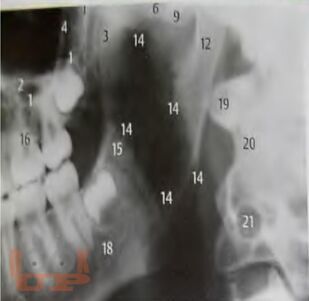

Алгоритм лучевой диагностики при синдроме болевой дисфункции височно-нижнечелюстного сустава

В учебно-методическом пособии представлен доступный алгоритм лучевой диагностики при синдроме болевой дисфункции височно-нижнечелюстного сустава. Алгоритм дает возможность повысить точность диагностики, а следовательно, и эффективность лечения пациентов, индивидуализировать методы терапии каждого больного.

Пособие предназначено для врачей разных специальностей: стоматологов, неврологов и рентгенологов, а также интернов и ординаторов.